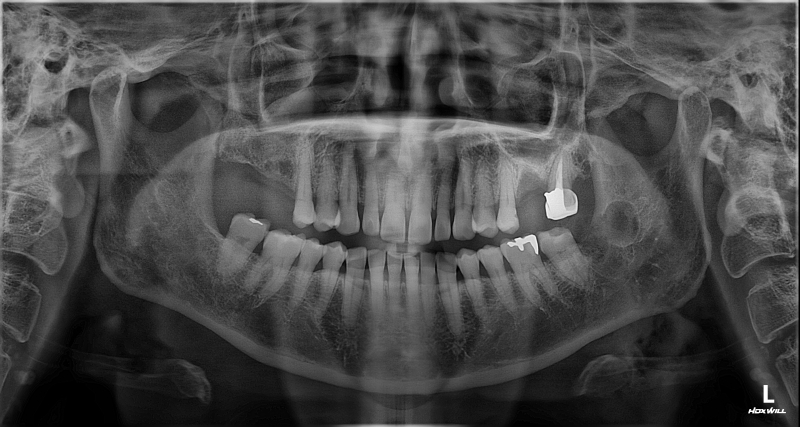

촬영일시: 2026.04.10